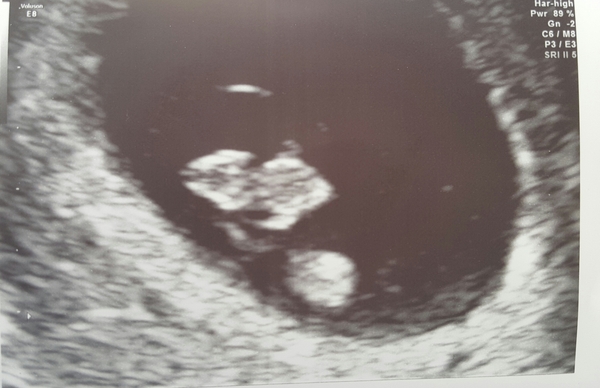

Finally had my scan... I'm only 7 weeks 5 days! BUT they could see a heart beat as clear as day and I have 'viable pregnancy' written on my notes. According to my consultant that's a good thing as odds of complications slash once a heartbeat has been seen :) so here's out little pumpkin seed ❤

Scan buddy Choc, such a good picture for 7 weeks! So strange that you got the false positives to begin with though.

Thank you everyone! Gobsmacked by the date! Totally wasn't expecting it but grearly reassured by such a clear heartbeat etc ☺☺ consultant can't explain the earlier stuff but to be honest I'm not fussed... desired result has been achieved and we have a happy pumpkin seed cooking away 😍😍

choc what the hell? How are you only 4 days more pregnant than me?! It makes no sense! Beautiful pumpkin seed though GrinFlowers